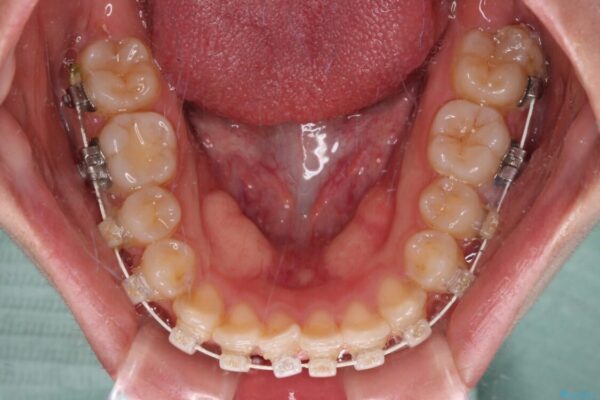

治療途中

• 【モニター】短期間で終わりたい ワイヤー装置での非抜歯矯正 治療途中画像